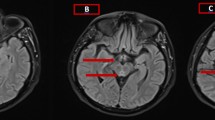

MRI sequences typically include, pre- and post-contrast (gadolinium) T1-weighted images with gadolinium, T2-weighted images, fluid-attenuated inversion recovery (FLAIR), diffusion-weighted imaging (DWI), and apparent diffusion coefficient (ADC) mapping. MRI has a sensitivity and specificity of 53% and 93%, respectively, for WE (Ogershok et al., 2002). The sensitivity may actually be higher, but MRI is often performed after the patient has been suspected of WE and empirically treated, resulting in a non-diagnostic study (Celik and Kaya, 2004). Good correlation has been found between contrast mediated magnetic resonance imaging (MRI) and neuropathological findings (Liu et al., 2006). Classically, T2-weighted and FLAIR MRI images reveal symmetrical increased signal intensity of areas including the third paraventricular regions of the thalamus and hypothalamus, periaqueductal regions of the midbrain and mammillary bodies. These lesions may sometimes be enhanced with gadolinium on T1-weighted images during an acute event and may dissipate with treatment (Chiossi et al, 2006; Mascalchi et al., 1999; Doherty et al., 2002; Halavaara et al., 2003). In one case, mammillary body enhancement was the only sign of acute WE (Shogry and Curnes, 1994). FLAIR sequences are reviewed to ensure that the cerebrospinal fluid has not masked high signal lesions on T2-weighted imaging (Chung et al., 2003). The chronic stage of WE may be depicted by brain atrophy and diffuse signal-intensity changes in the cerebral white matter (White et al., 2005).

Although there is insufficient evidence to suggest the presence of cytotoxic edema in acute WE, there is good evidence for vasogenic edema (Liu et al., 2006). The advantage of DWI over T2-weighted and FLAIR imaging is its ability to better distinguish between cytotoxic and vasogenic edema (Chiossi et al., 2006; Chung et al., 2003). DWI, in conjunction with ADC mapping, is particularly useful, as it is the most sensitive method for diagnosing early injury, i.e. vasogenic edema, before the onset of necrosis, thus facilitating early diagnosis of WE (Doherty et al., 2002; Halavaara et al., 2003). Cytotoxic edema is represented by high intensity signal on DWI with corresponding low signal on ADC mapping. Vasogenic edema, however, will show high signal intensity on both DWI and ADC mapping (Weidauer et al., 2004).